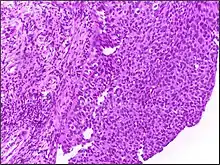

![]() | Dysgerminoma | Dysgerminoma characterized by uniform cells resembling primordial germ cells separated by fibrous septa with lymphocytes. | Category: Histopathology of ovarian dysgerminoma | Ovarian dysgerminoma |